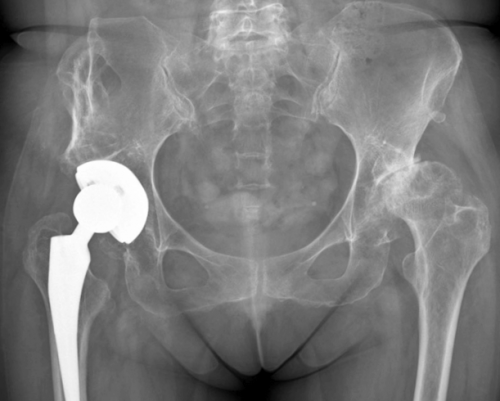

Рентгенография ТБС. Остеосинтез перелома устройствами <

или разрушением сустава, является эндопротезирование.

выраженном остеоартрите, требующем замены тазобедренного

хирургическая операция (при переломе, асептическом некрозе или

Таким образом, пациентам может рекомендоваться установка эндопротезов разного вида. Большинство эндопротезов для замены тазобедренных суставов производятся на территории США и Великобритании. Для их изготовления используются химически и биологически инертные металлы: кобальт, хром, титановые сплавы. Нередко также применяется керамика. В большинстве современных моделей дополнительно используются полимерные прокладки, которые позволяют обеспечить естественные амортизационные, стабилизационные и скользящие свойства искусственному ТБС.

Операция выполняется под общим наркозом и занимает около часа. В зависимости от тяжести дегенеративно-дистрофического процесса операция может проводиться по одной из следующих методик:Артродез – доступная операция, подразумевающая прочную фиксацию суставных костей металлическими пластинами. В результате достигается полное обездвиживание сустава. Поэтому с помощью артродеза можно исправить только опорную функцию ноги, устранить боли, но говорить о восстановлении подвижности или существенном повышении качества жизни не приходится.• перелом шейки бедра.При запущенной патологии операция является вынужденно необходимой мерой. Лишь своевременно проведенное хирургическое вмешательство поможет восстановить нормальную подвижность и избавить пациента от мучительных болей, т. е. добиться существенного повышения качества жизни человека. Никакие лекарственные средства, физиотерапевтические процедуры, не смогут восстановить сильно разрушенный хрящ. В лучшем случае болезненные внутрисуставные инъекции и препараты смогут уменьшить болевой синдром. Но это будет временным явлением, после которого боли снова вернуться с прежней или даже большей силой.

нескольких дней, в тяжелых случаях на бок или Таким образом, коксартроз ТБС – довольно грозное заболевание, способное напрочь лишить человека возможности самостоятельно передвигаться. Оно прогрессирует в течение длительного времени, а его симптомы, особенно на ранних стадиях, зачастую воспринимаются больными в качестве нормального состояния после физических нагрузок. Но именно в этом и кроется коварство болезни, ведь только на начальном этапе ее развития с ней можно справиться безоперационным путем. Но если дегенеративно-дистрофический процесс уже полностью разрушил гиалиновый хрящ и привел к оголению поверхностей костей и тем более их сплющиванию, пациенту может помочь только операция. Благо, современный уровень медицины и хирургии в частности позволяет добиться полного восстановления нормального состояния тазобедренного сустава и его функций.• тотальная – самый эффективный и безопасный метод решения проблемы коксартроза ТБС, подразумевающий полную резекцию головки бедренной кости с захватом части ее шейки, а также вертлужной ямки и замену их полноценным искусственным суставным сочленением.

Операция подразумевает резекцию головки бедренной кости и частично ее шейки. Также проводится хирургическая подготовка вертлужного ложа, подразумевающая удаление остеофитов, выравнивание его поверхности и резекцию подвергшихся некрозу тканей. Эндопротезирование может использоваться даже для лечения больных коксартрозом ТБС пожилого возраста.• остеотомия.• критические нарушения подвижности;Несмотря на существенный дискомфорт в ТБС, многие обращаются за медицинской помощью слишком поздно, когда патологические изменения в суставе достигают 3 или даже 4 степени тяжести, а функциональные возможности необратимо истощены.• парафинолечения.• магнитотерапии;Занятия ЛФК позволяют улучшить кровообращение в области протекания дегенеративно-дистрофического процесса. Благодаря этому повышается качество трофики больного сустава и ускоряется течение регенеративных процессов.

паха, бедро.ДТП и спортивных исчезает в течение сустава. Возникает при падении Остеотомия – хирургическое вмешательство, являющееся временной мерой перед кардинальной заменой тазобедренного сустава искусственным эндопротезом. Суть операции заключается в выравнивании оси бедренной кости за счет намеренного ее перелома. Образовавшиеся фрагменты устанавливают в наиболее приемлемом положении, тем самым немного разгружая больной сустав. В результате на время удается уменьшить выраженность болей и добиться улучшения подвижности.• биполярная – аналогичная предыдущей методика, отличающаяся только конструкцией используемого эндопротеза, который имеет более низкий коэффициент трения и обеспечивает более плавные движения в суставном ложе;Эндопротезирование с артропластикой – единственный способ радикального решения проблемы коксартроза тазобедренного сустава с восстановлением всех его функций и двигательных возможностей. Это высокотехнологичный метод решения проблемы коксартроза, позволяющий на 15—30 лет полностью забыть о нем, как и о болях, и ограничениях подвижности. Благодаря использованию современных эндопротезов удается добиться восстановления двигательно-опорных функций в полной мере и обеспечить больному нормальную жизнь.• эндопротезирование;• стойкие боли в ТБС, не поддающиеся купированию;Хирургическое лечение коксартроза тазобедренного сустава• УВЧ;